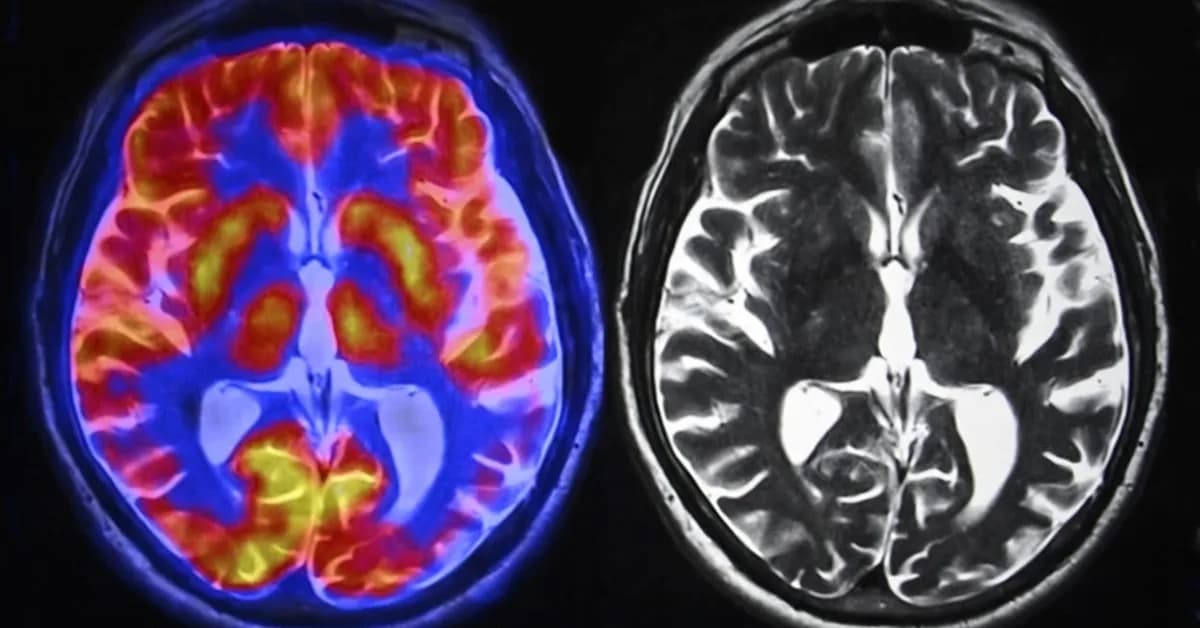

- Brain Activity Changes: Studies show that using LLMs can reduce brain activity in areas associated with problem-solving and critical thinking.

- Neural Pathways Alteration: Frequent use of AI tools may lead to a shift towards more passive cognitive pathways, potentially diminishing the development of analytical skills.

- Neuroplasticity Benefits: AI-assisted learning that promotes active problem-solving may actually strengthen neural connections associated with cognitive flexibility and creativity.